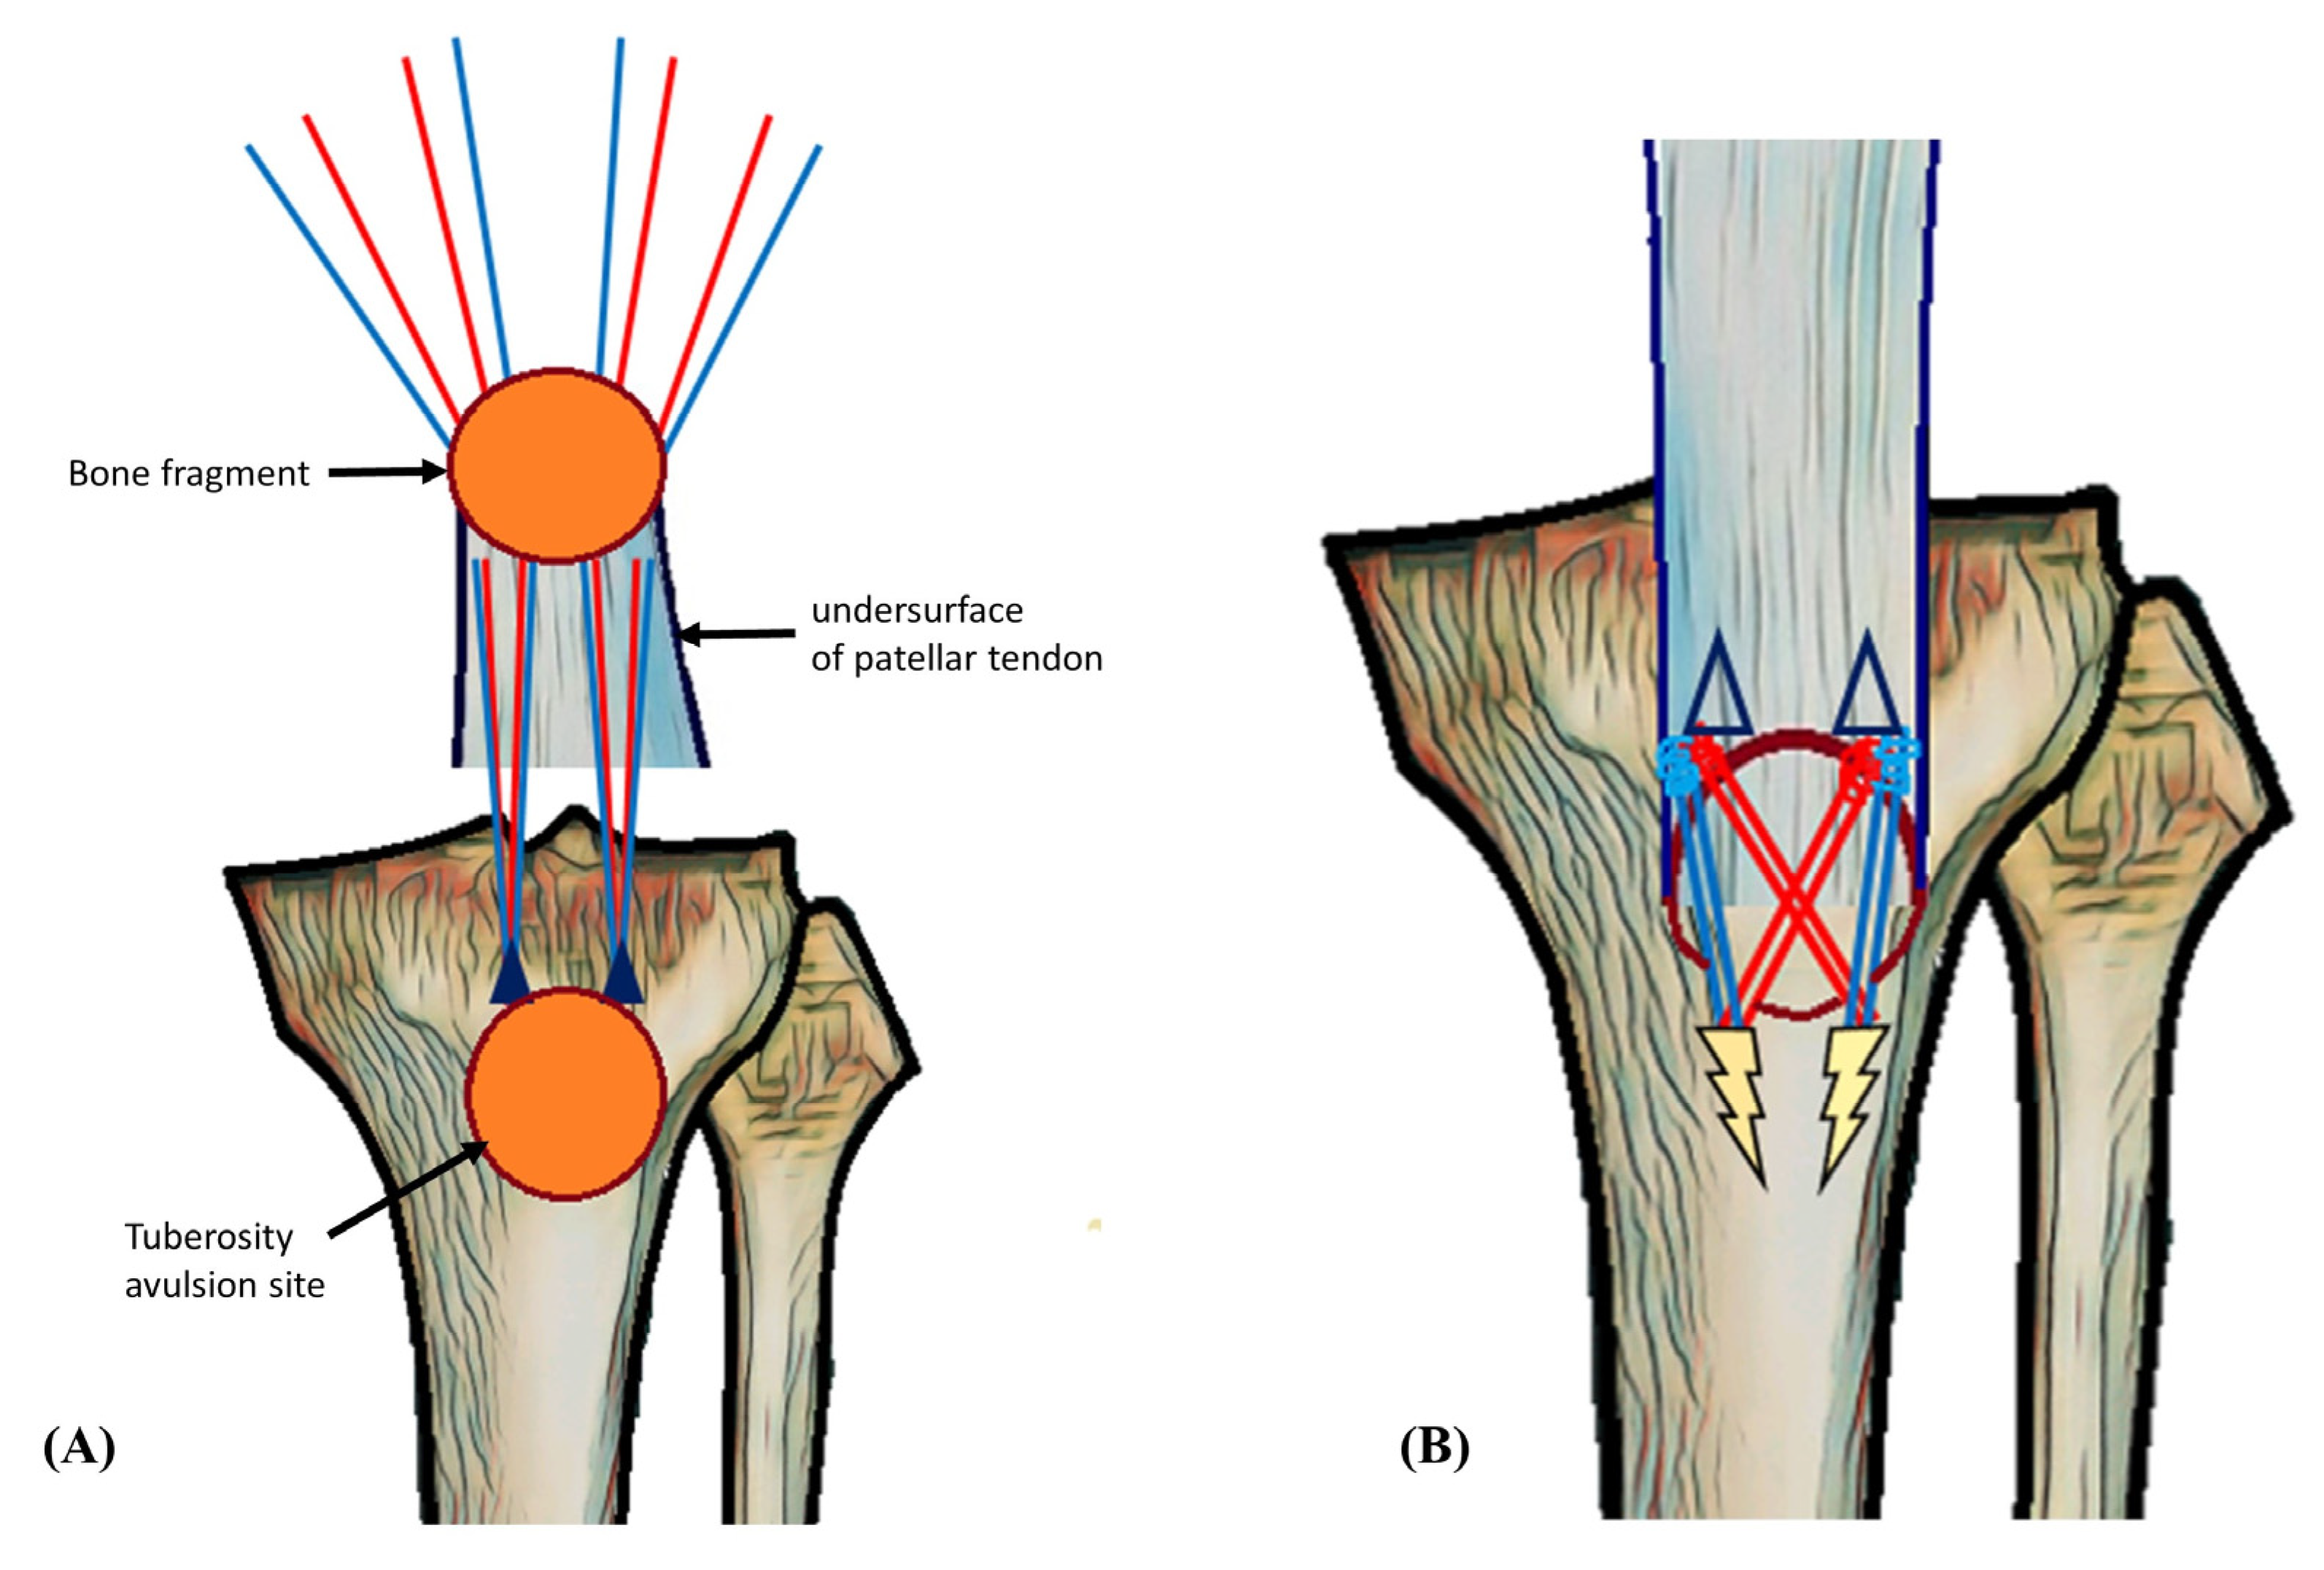

Isolated Avulsion Fracture of the Tibial Tuberosity in an Adult Treated with Suture-Bridge Fixation: A Rare Case and Literature Review

2. Case Presentation